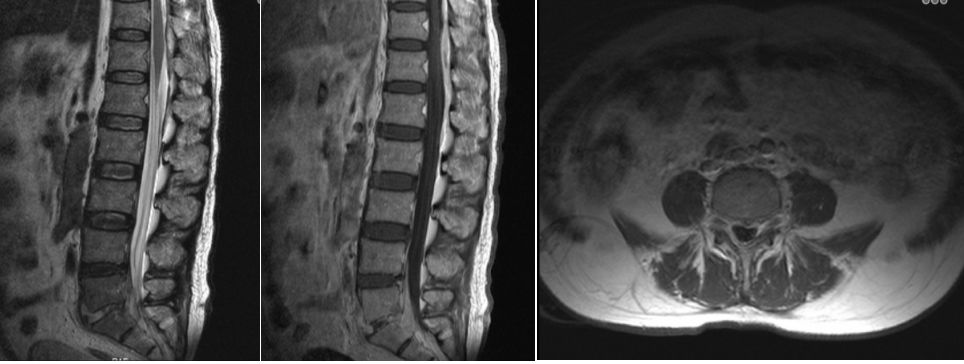

术后病理证实为感染化脓性炎症(图2B)。患者疼痛症状明显缓解,左下肢肌力较术前改善,经继续予抗感染治疗,术后2周复查白细胞计数4.9×10^9/L,超敏C-反应蛋白5.6mg/L,炎症控制满意,切口愈合良好(图2C)。MRI复查显示局部减压效果良好,硬膜外脓肿占位消失(图3)。

图3. MRI复查显示局部减压效果良好,硬膜外脓肿占位消失。